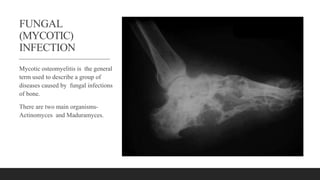

FUNGAL

(MYCOTIC)

INFECTION

Mycotic osteomyelitis is the general

term used to describe a group of

diseases caused by fungal infections

of bone.

There are two main organisms-

Actinomyces and Maduramyces.